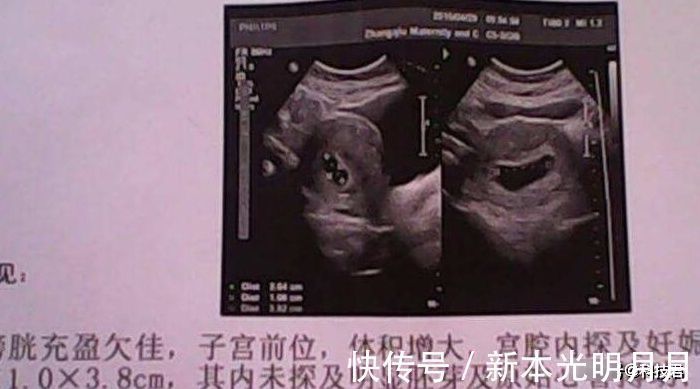

4、胎囊

在孕早期,第一次做B超检查的时候,只能看到孕囊,虽然看起来很小,但是如果孕妈想要通过,这个来知道胎儿的性别的话,孕妈可以仔细的观察孕囊的形状,如果孕囊的形状是长椭圆形的,那么,很可能会生个男宝宝。